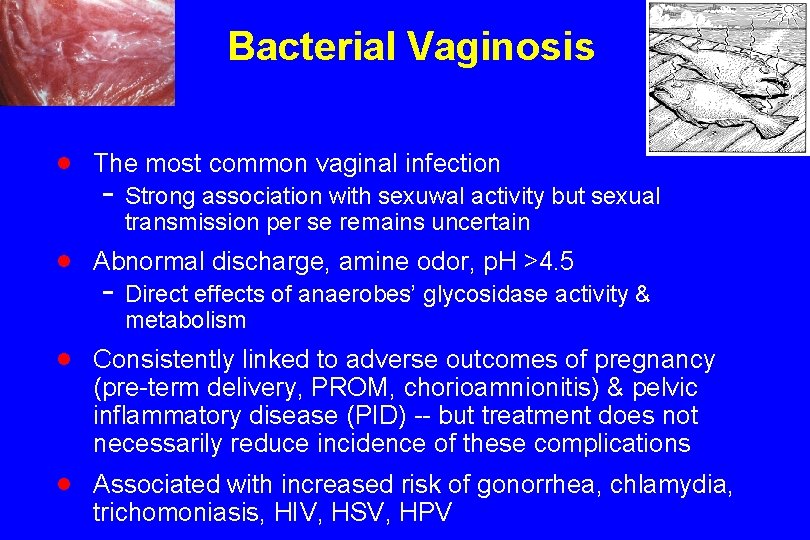

Bacterial Vaginosis · The most common vaginal infection - Strong association with sexuwal activity but sexual transmission per se remains uncertain · Abnormal discharge, amine odor, p. H >4. 5 - Direct effects of anaerobes’ glycosidase activity & metabolism · Consistently linked to adverse outcomes of pregnancy (pre-term delivery, PROM, chorioamnionitis) & pelvic inflammatory disease (PID) -- but treatment does not necessarily reduce incidence of these complications · Associated with increased risk of gonorrhea, chlamydia, trichomoniasis, HIV, HSV, HPV